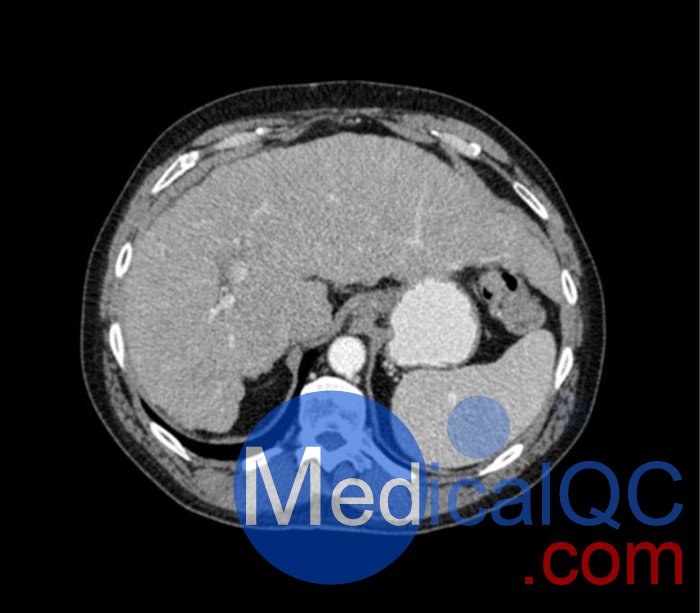

WEK53-04肝硬化腹部模體,WEK53-04腹部模體代表膽囊切除術(shù)后的腹部,帶有小夾子。肝臟有肝硬化的典型體征,在第三腰椎水平植入下腔靜脈過濾器。兩個腎臟都有囊性病變,左側(cè)有一小塊腎結(jié)石。

真實模擬脈管系統(tǒng)、骨骼和軟組織,包括肝臟、胰腺、脾臟、腎上腺、腎臟、胃、小腸和結(jié)腸。

• 肝硬化